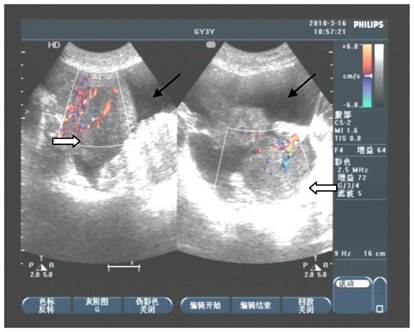

Figure 2

Abdominal ultrasound detection appeared that lumps in bilateral ovaries with rich blood supply (⇒). Fluid sonolucent areas were seen besides ovaries (→).